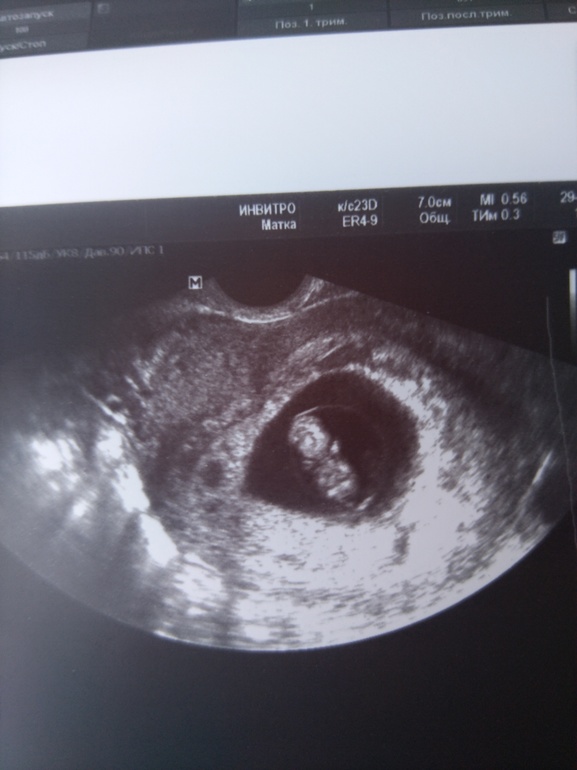

Мама девочки (6 лет), жду девочку, 11 неделя

8 недель перестала болеть и слегка опала хрудь((

Пошла на УЗИ

А там моя матрёшка уже с датчиком бодается во всю. Опережает развитие на 4 дня. 8 нед ,4 дня поставили . отслоек нет, СБ отличное . 176 ударов. А мать параноик))

😆 Ну как как, рассмотрела глазами) мордашка внизу, белым лобик выделяется, чють выше по бокам белые точечки - глазки. Ну понятное дело все ещё зачаточное, на кого похож будет пока не скажешь 😂😂😂

Белые «точки» по бокам-это ручки )) Если ошибаюсь-автор поста меня исправит ))

Ой, девки, насмешили))) руки то руки, они после головы и уже не точки, а глаза на голове))))

Она ж еще несколько дней назад креветочкой была, а тут уже человек мордашку формирует, делом занят и мамкиной хрудью) некогда заниматься)))